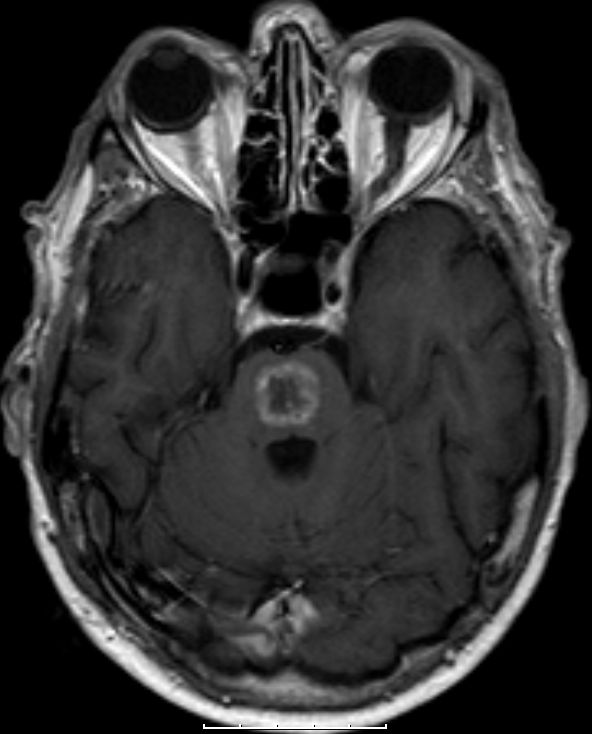

| MRT: multiple Hirnmetastasen | Adenokarzinom der Lunge. MRT-Untersuchung des Hirns. | |||

![]() |